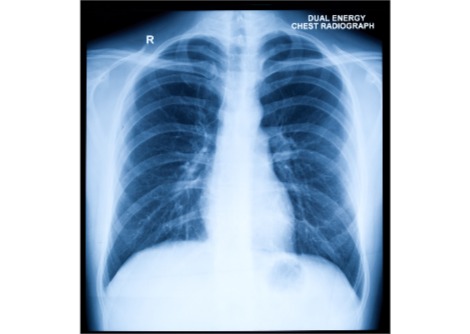

يتطلّب تتبّع المؤشرات الحيوية الداخلية، مثل البروتينات المرتبطة بالالتهاب أو المرض، عادةً عينات دم أو أجهزة استشعار خارجية مؤقتة. لا تُقدّم هذه الطرق سوى لمحات سريعة، وغالبًا ما تتطلّب اختبارات متكررة.